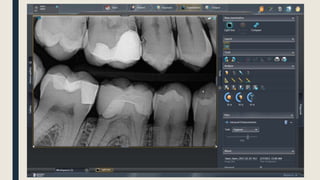

PSP Imaging

• Displaying an image on a PC is much better than displaying it on printed films on an x-ray viewer

• You can manipulate the image, by changing the brightness and contrast, and you can do several

post enhancements on the image such as changing the sharpness, smoothness, inverting B/W,

colorize and even do some extra advanced filters so the image appears better

• You can also save patients’ data and manage files for all patients on the software easily